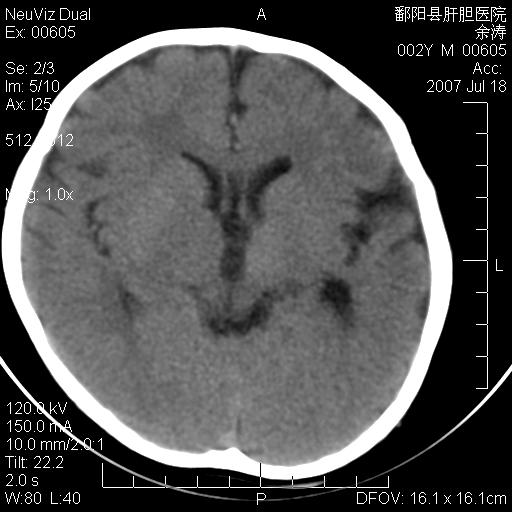

男性 2岁:平时智力障碍。外伤后行颅脑平扫。

左颞叶“萎缩”,可见不规则高密度影,并左侧室扩大,呈负占位效应...支持考虑先天发育异常(血管发育畸形)可能性大,建议结合进一步检查了解。

脑裂畸形;左侧脑脑萎缩;透明隔囊肿;血管畸形?

开唇型脑裂畸形

该病人应该还有胼胝体发育不全